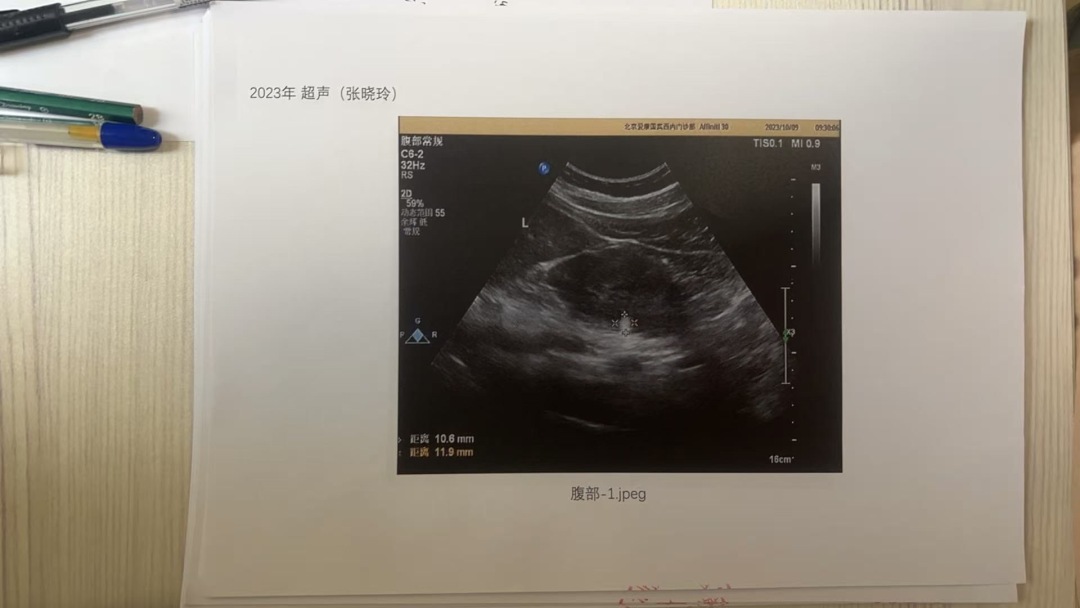

张晓玲对记者表示,自今年7月17日公开向爱康国宾索要病历至今,其未向她提供10年完整真实的超声影像。12月5日,在北京市卫生健康委的主持下,其仅在12月8日提供了2021年、2022年、2023年的三年超声影像图片复印件。

张晓玲称,爱康国宾提供的超声影像无姓名、ID等信息